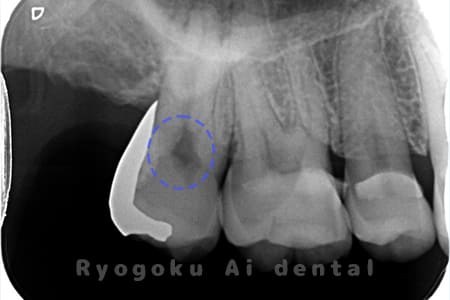

Case04

-

- 原因

- C3、重度カリエス

- 治療内容

- 17・15断髄治療

- 治療費用

- 154,000円

他院で神経をとるほどの虫歯があり、神経を残したいとのことで来院された患者様です。歯の神経を一部分取る断髄治療を行い、問題なく経過を追っています。

<リスク・副作用>

術後は痛み、腫れ、痺れなどの副作用が生じる場合があります。症状が再発する可能性があります。その場合は抜髄する必要があります。